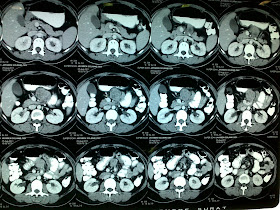

CECT:

EUS : FNAC / BX : S/O malignant tumor.

SURGERY: EXCISION OF TUMOR.

pt was discharged on POD 5, with normal DIET.  FINAL HPE with IHC awaited.